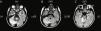

En la tomografía computarizada craneal realizada el día del debut de la clínica neurológica no se apreciaban imágenes patológicas significativas (fig. 1). En la resonancia magnética de cráneo y columna al día siguiente se observaba una hiperintensidad en T2 (fig. 2) y FLAIR (fig. 2 B y C) que afectaba a vermis y hemisferio cerebeloso derecho, principalmente en su porción superior y media sin otras alteraciones destacables.

De los pocos casos clínicos de cerebelitis por rotavirus descritos previamente, la mayoría se han comunicado en Japón, casi siempre en asociación con clínica de encefalitis, con afectación del sensorio. La afectación exclusiva del cerebelo de forma bilateral debida a este patógeno ha sido comunicada previamente en escasas ocasiones7. En la hemicerebelitis asociada a rotavirus que presentamos, la evolución mostrada fue benigna, no se asociaron convulsiones ni alteración del nivel de conciencia. El manejo del caso pudo ser conservador, con una resolución ad íntegrum de sus síntomas. El diagnóstico fue clínico apoyado en el estudio por RMI craneal. Las imágenes por TC al debut fueron normales.